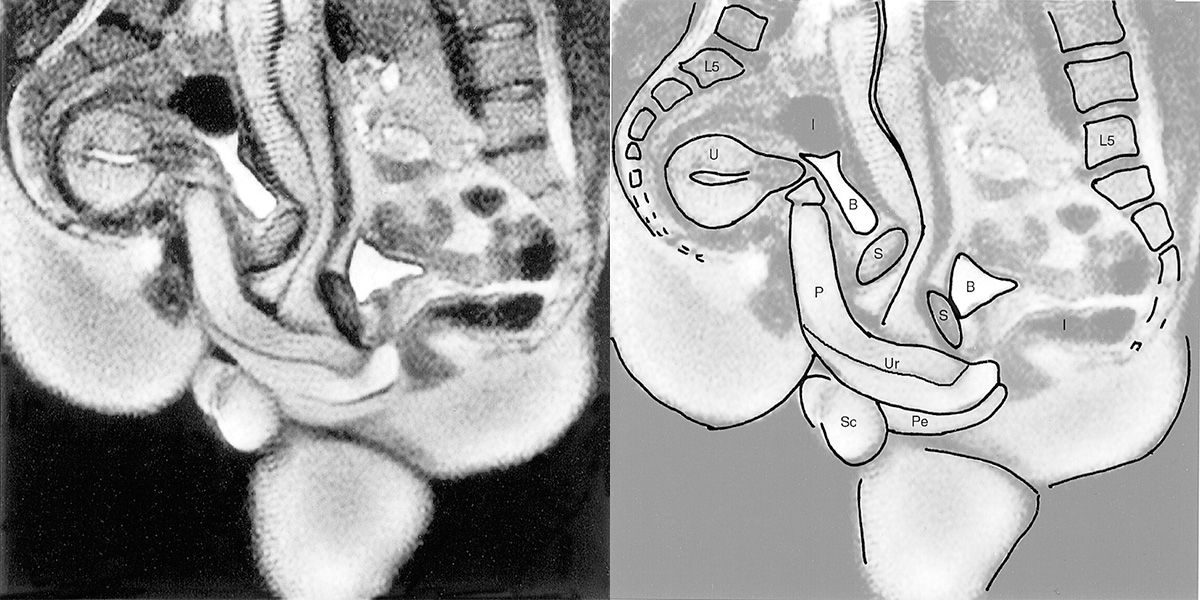

Links das Originalbild, rechts eine vereinfachte Darstellung des Geschlechtsverkehrs: P=Penis, Ur=Harnröhre, Pe=Damm, U=Uterus, S=Symphyse, B=Blase, I=Darm, L5=Lumbal 5, Sc=Hodensack